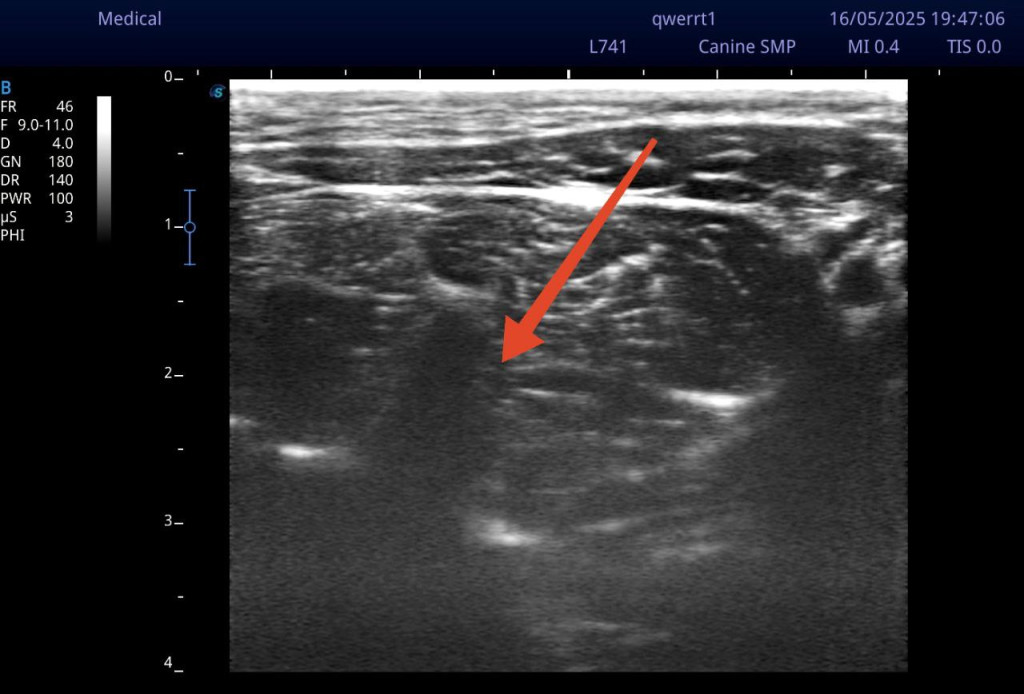

Датчик УЗИ располагается на латеральной поверхности шеи, поперек плоскости оси шейных позвонков (рис. 5). Сканирование начинается от первого шейного позвонка, смещаясь каудально. Шейные позвонки с первого по третий имеют характерные анатомические отличия, облегчающие идентификацию необходимых структур. Стоит уточнить, что кости на УЗИ не просвечиваются, так как ультразвук отражается от поверхности кортикального слоя, формируя изображение. Первый шейный позвонок (атлант) при УЗ-сканировании латеральной поверхности шеи имеет характерные анатомические особенности. Крылья атланта имеют значительную длину и ширину, что позволяет пропальпировать их перед сканированием и установить датчик в эту область, сразу обнаружив на экране силуэт, напоминающий большую тонкую волну, вершина которой направлена перпендикулярно плоскости сканирования. Второй шейный позвонок (эпистрофей/аксис) характеризуется самым маленьким, едва различимым при сканировании поперечным отростком, но отличается довольно массивными суставными отростками. К тому же поперечный отросток эпистрофея может частично перекрывать визуализацию вентрального бугорка поперечного отростка третьего шейного позвонка. Третий и последующие шейные позвонки имеют схожую типичную анатомическую структуру. Основной мишенью визуализации при блокаде будут именно поперечные отростки шейных позвонков. В своем составе поперечный отросток в его краниальной части имеет маленький вентральный бугорок, который при сканировании будет определяться как небольшой выступ, направленный к плоскости сканирования под углом примерно 45°. В каудальной части также имеется более длинный дорсальный бугорок, который чаще обращен к плоскости сканирования перпендикулярно. Таким образом, чередуя вентральные и дорсальные бугорки, можно безошибочно определить необходимый нам анатомический ориентир.

При визуализации дорсального бугорка третьего шейного позвонка можно увидеть фасцию, прилегающую к поперечным отросткам, в виде гиперэхогенной линии, отходящую перпендикулярно (при этом параллельно сканированию). Введение спинальной иглы осуществляется с вентролатеральной стороны в фасциальное пространство между длинной мышцей шеи и длинной мышцей головы до соприкосновения с поперечным отростком (рис. 6, 7).

Для выполнения данной хирургической манипуляции, помимо общей анестезии, индуцированной пропофолом и поддерживаемой ингаляционной анестезией с помощью изофлурана, была проведена блокада лестничной мышцы под контролем УЗИ (видео 2). Техника выполнения блокады лестничной мышцы схожа с методикой блокады длинной мышцы головы за исключением необходимости идентифицировать четвертый шейный позвонок с краниальной его части, при этом целевой точкой будет вентральный бугорок поперечного отростка С4. Он визуализируется как акустическая тень от кортикального слоя вентрального бугорка, направленная перпендикулярно к поверхности сканирования. Над бугорком определяется структура, напоминающая «шапочку», которая является лестничной мышцей.